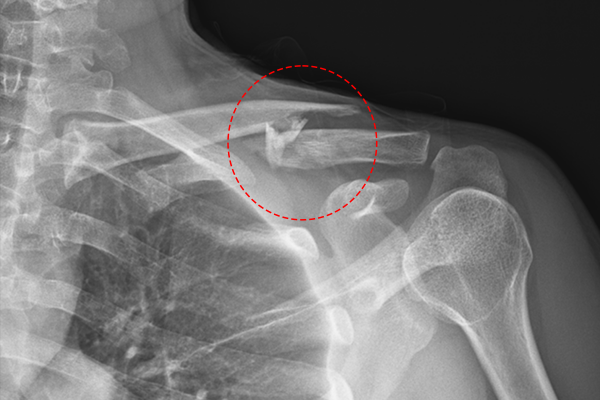

20ac6334118c27e0cf78b5d1504f202d_1767861880_2342.png

수술은 실시간 X-RAY인 C-ARM을 이용하여 확인하며, 분쇄골절된 뼈를 맞춰줍니다. 이때 골편을 일일이 닭고기 발라내듯 정확하게 맞추려 하거나 골절면을 과도하게 긁어내려 하면, 혈류와 골막이 손상되어 오히려 뼈가 붙지 않는 불유합을 유발할 수 있습니다.(골절면을 과도하게 긁어내 불유합이 발생하면 뼈가 유합되지 않았는데 힘이 가해지면서 금속판이 부러지거나 스크류 헤드와 쓰레드(thread, 나사산) 사이에서 파절이 될 수 있습니다.)

분쇄골절 치료의 핵심은 골절선을 침범하지 않는 범위 내에서 전체적인 축과 형태만 맞춰놓는 것이며, 시간이 지나면 골진이 형성되면서 자연스럽게 뼈가 엉겨 붙게 됩니다.(일부에서는 분쇄된 쇄골뼈를 와이어로 감아 고정하려는 경우가 있으나, 이러한 방식은 오히려 유합에 도움이 되지 않는 경우가 많습니다.)

골절된 쇄골 뼈를 정복 후 K-wire를 이용하여 임시고정한 후 금속판(Plate)으로 강하게 고정해줍니다.

20ac6334118c27e0cf78b5d1504f202d_1767861890_722.png

수술 후 X-RAY를 보면 정상적인 우측 쇄골뼈와 라인이 맞게 잘 정복 및 고정된 것을 확인할 수 있습니다.